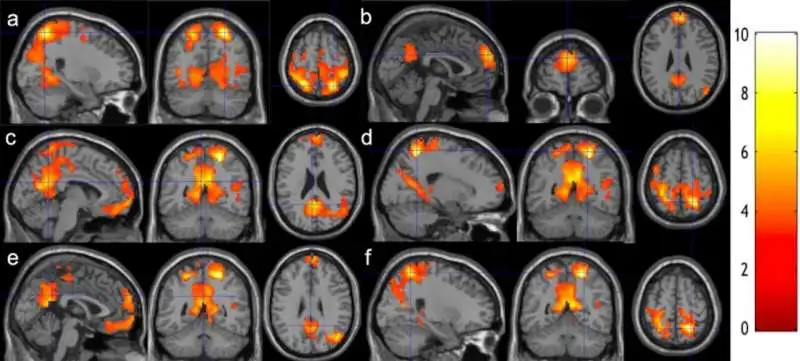

The following are real brain scans performed by legit experts in their fields; more information about each experiment will be linked.

Researchers conducted a study scanning some of their students' brains before and after eight weeks of practising meditation under a professional trainer. This study emphasises how just two months into meditation can show intriguing results.

These MRI scans revealed significant changes in some brain patterns, explaining the impact of meditation on cognition and overall neural activity. This research knew light thanks to a casual chat between Assistant Professor Weijying Dai and Lecturer Gorge Weinschenk. Both are experts in longtime meditation, brain mapping and biochemical image processing, more details can be found Within The official study Publication. Sources: Research shows just 8 weeks of meditation studies can make your brain quicker

2. Noobs vs Experts in Meditation: University of Wisconsin and its affiliates study

This study focused on learning about what makes long-term meditators vs novices. What makes the difference within their brains? And How it reflected in their lives.

Functional resonance imaging (fMRI) revealed distinct patterns in emotions-related brain networks, showing that long-term meditators dedicated to mindfulness and meditation experiences exhibited unique neural connectivity. Sources: Meditation affects brain networks differently in long-term meditators and novices -Impact of short- and long-term mindfulness meditation training on amygdala reactivity to emotional stimuli

Researchers at Massachusetts General Hospital used MRI scans to observe changes in gray matter associated with mindfulness meditation. Gray matter refers to the parts of the brain that contain cell bodies and synapses, and it plays a crucial role in processing information and regulating emotions.

The findings of this study add to a growing body of research supporting the idea that meditation can induce neuroplasticity, the brain's ability to reorganise and form new connections in response to experience.